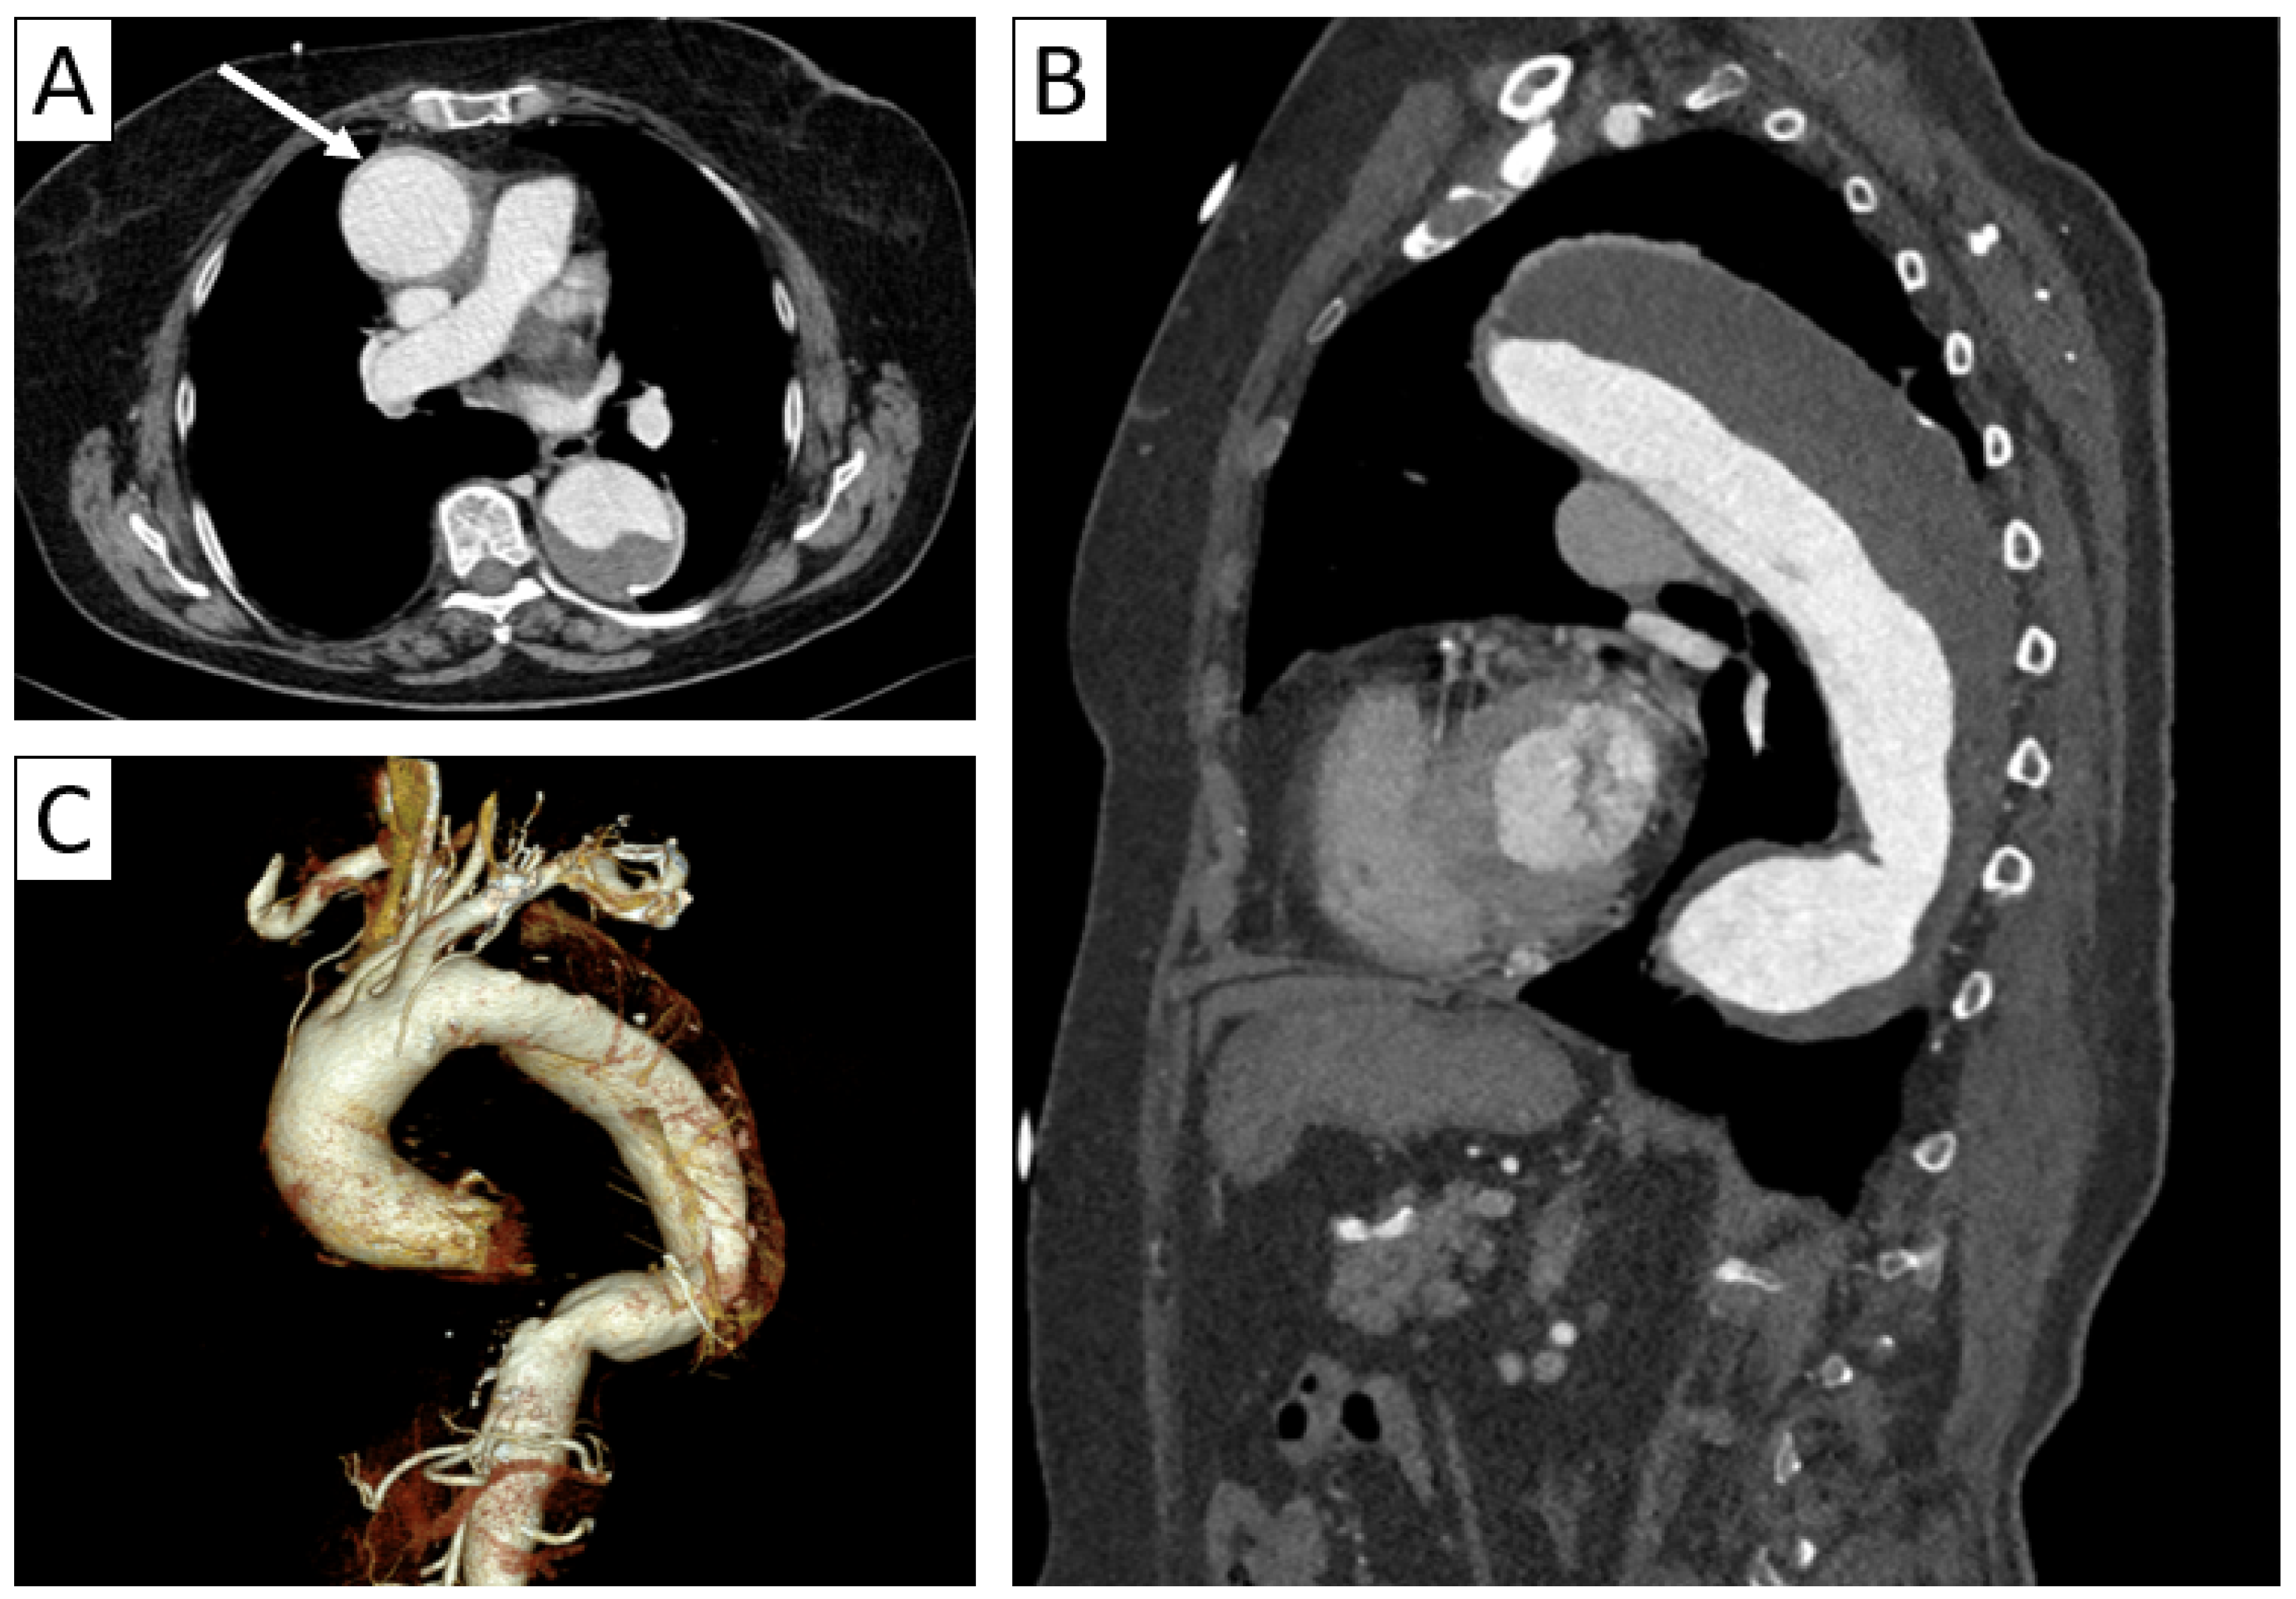

| CTA | Circumferential parietal thickening Vessel wall enhancement | Circumferential parietal thickening Vessel wall enhancement Luminal stenosis or narrowing |